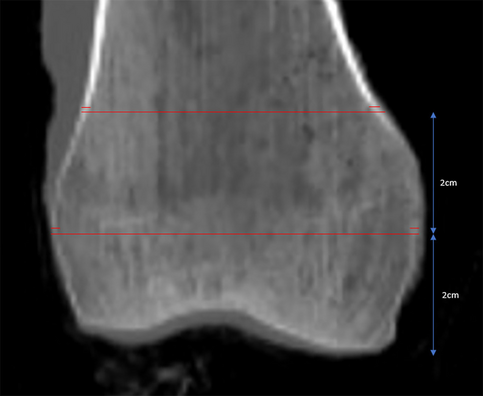

The specimens underwent standard clinical Discovery CT750 HD CT scans (General Electric, Madison, WI). Picture Archiving and Communication Systems (PACS) was used for measurements. Cortical width (the linear distance between the outer edges of the femoral cortex) and cortical index (the ratio of the sum of the medial and lateral cortical width divided by the entire width of the bone) were measured at two levels within the distal femur (Fig. 1). Measurements were performed three times by one author (JTB) and averaged. The locations (i.e., 2 and 4 cm proximal to the most distal point of the distal femoral condyles) were chosen to represent two locations of screw clusters in a standard distal femoral locking plate. HU were obtained on axial CT slices at the same two levels in the distal femur. An elliptical region of interest (ROI) was drawn as large as possible without including the cortical bone (Fig. 2).

Fig. 1

Representative measurements of cortical width and cortical index on a mid-coronal CT image of the distal femur. Measurements are made at 2 and 4 cm proximal to the most distal aspect of the bone